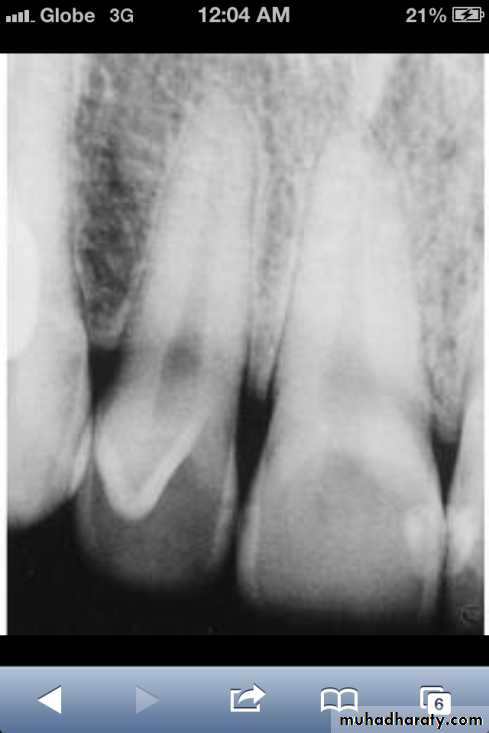

• Fusion of the left mandibular central and lateral incisors (twoindividual roots, two root canals and two joined crowns).

Gemination of right mandibular central incisor has one root, one root canal and a partially bifid dental crown.